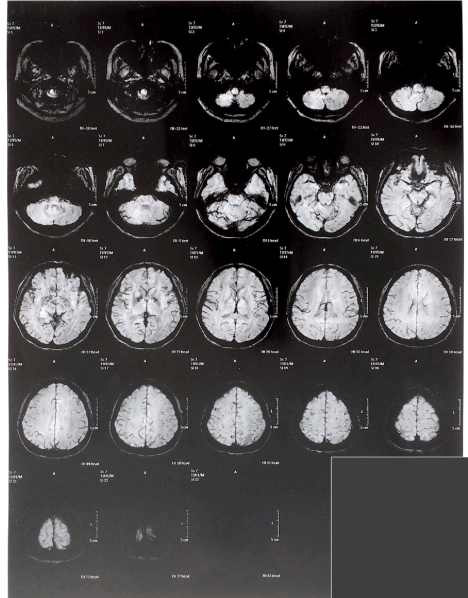

In a new clinical interview, the patient reported that the headaches began after the birth of her second child and increased after reaching the age of 45 years. No family history of migraine, neuropsychiatric disorders, substance abuse has been reported. Neurological examination indicated slight impairments in information processing speeds. Ophthalmologic examination indicated intraocular pressure of 17.09 ± 2.25 and no abnormalities were observed in the specular corneal microscopy exam. The patient reported no symptoms such as photosensitivity or epileptic seizures, but mentioned that a complete battery of exams had been performed previously. Conventional electroencephalography (EEG) and magnetic resonance imaging (MRI) studies comprising T1, T2 and Flair (Figure 1) were performed.

Figure 1. Flair MRI showing microangiopathy in the frontal horn

In a new neurological evaluation, the neurosurgeon indicated that the MRI results for T1 and T2 really did not indicate clinical significance. However, SWI showed calcification of the basal ganglia, and in Flair a slight microangiopathy was observed in the frontal horn.